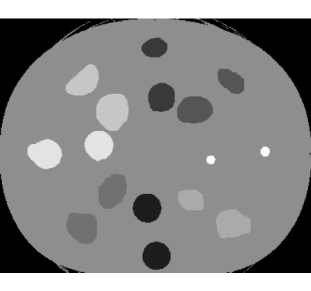

where is the number of pixels in object , are the pixels in object , and is the Euclidean distance between the coordinates of pixel and pixel . The locations of the pixels can be obtained from an exemplar image that has been manually labelled. The mean is the average spatial displacement of the object between images, while the variance represents the degree of uncertainty. Fig. 1 illustrates external field priors with increasing levels of spatial uncertainty for the ED phantom that is described in Section 4.

The external field prior was precomputed according to Eq. (5). This prior was centred on the geometry of the ED phantom at 0 offset. We used a mean displacement of with standard deviation . This spatial variability corresponds to the prostate motion observed by Frank et al. (2008) in their study of 15 radiotherapy patients. The external field is illustrated in Fig. 3a.

The amount of spatial variability in our application is quite small (standard deviation of ) relative to the size of the images (). We reran the model using external field priors with increasing levels of uncertainty ( up to , illustrated in Fig. 1) to measure the relationship between the strength of the prior and the resulting segmentation accuracy. The pixel-wise misclassification rates for the 27 cone-beam CT scans are shown in Fig. 4. We found that there was a strong relationship, with the proportion of misclassified pixels increasing sharply at first, but then gradually levelling off. As the uncertainty increases, we would expect that the misclassification rate would approach 86.8%, the accuracy that is observed without the external field prior.